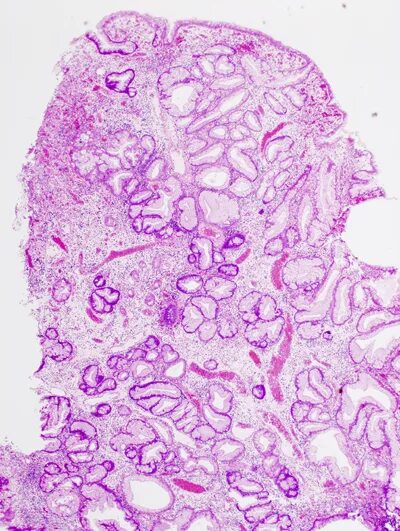

Микровезикулярный тип это